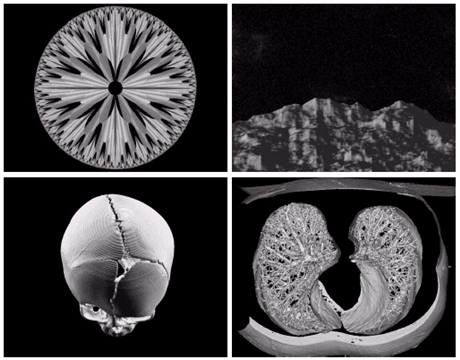

• 전자현미경: SEM(scanning electron microscope)

• 전자빔을 쏘아 각 위치에서 빔과 샘플과의 상호작용을 기록

Image

텅스텐필라멘트의 250x SEM영상, 손상된 IC의 250x SEM영상